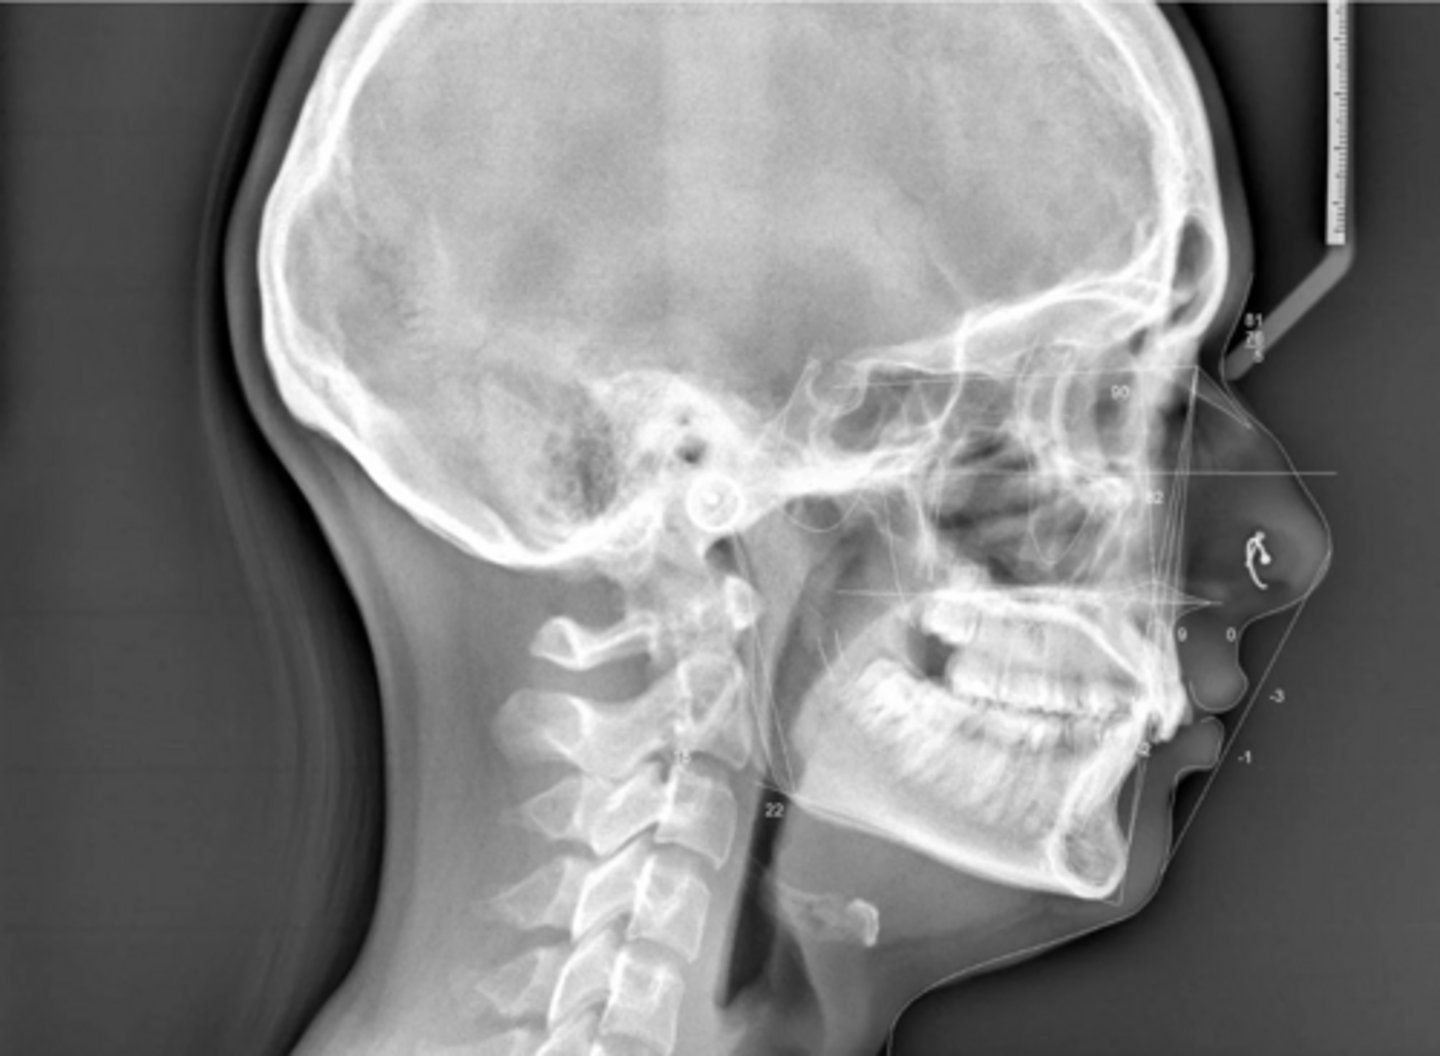

Class II

What type of skeletal malocclusion is this patient?

Hyperdivergent

Are the hyper-, hypo-, o normo- divergent?